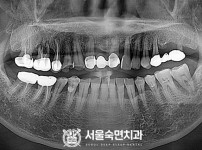

임플란트-전후사진1

임플란트-전후사진2

임플란트-전후사진3

임플란트-전후사진4